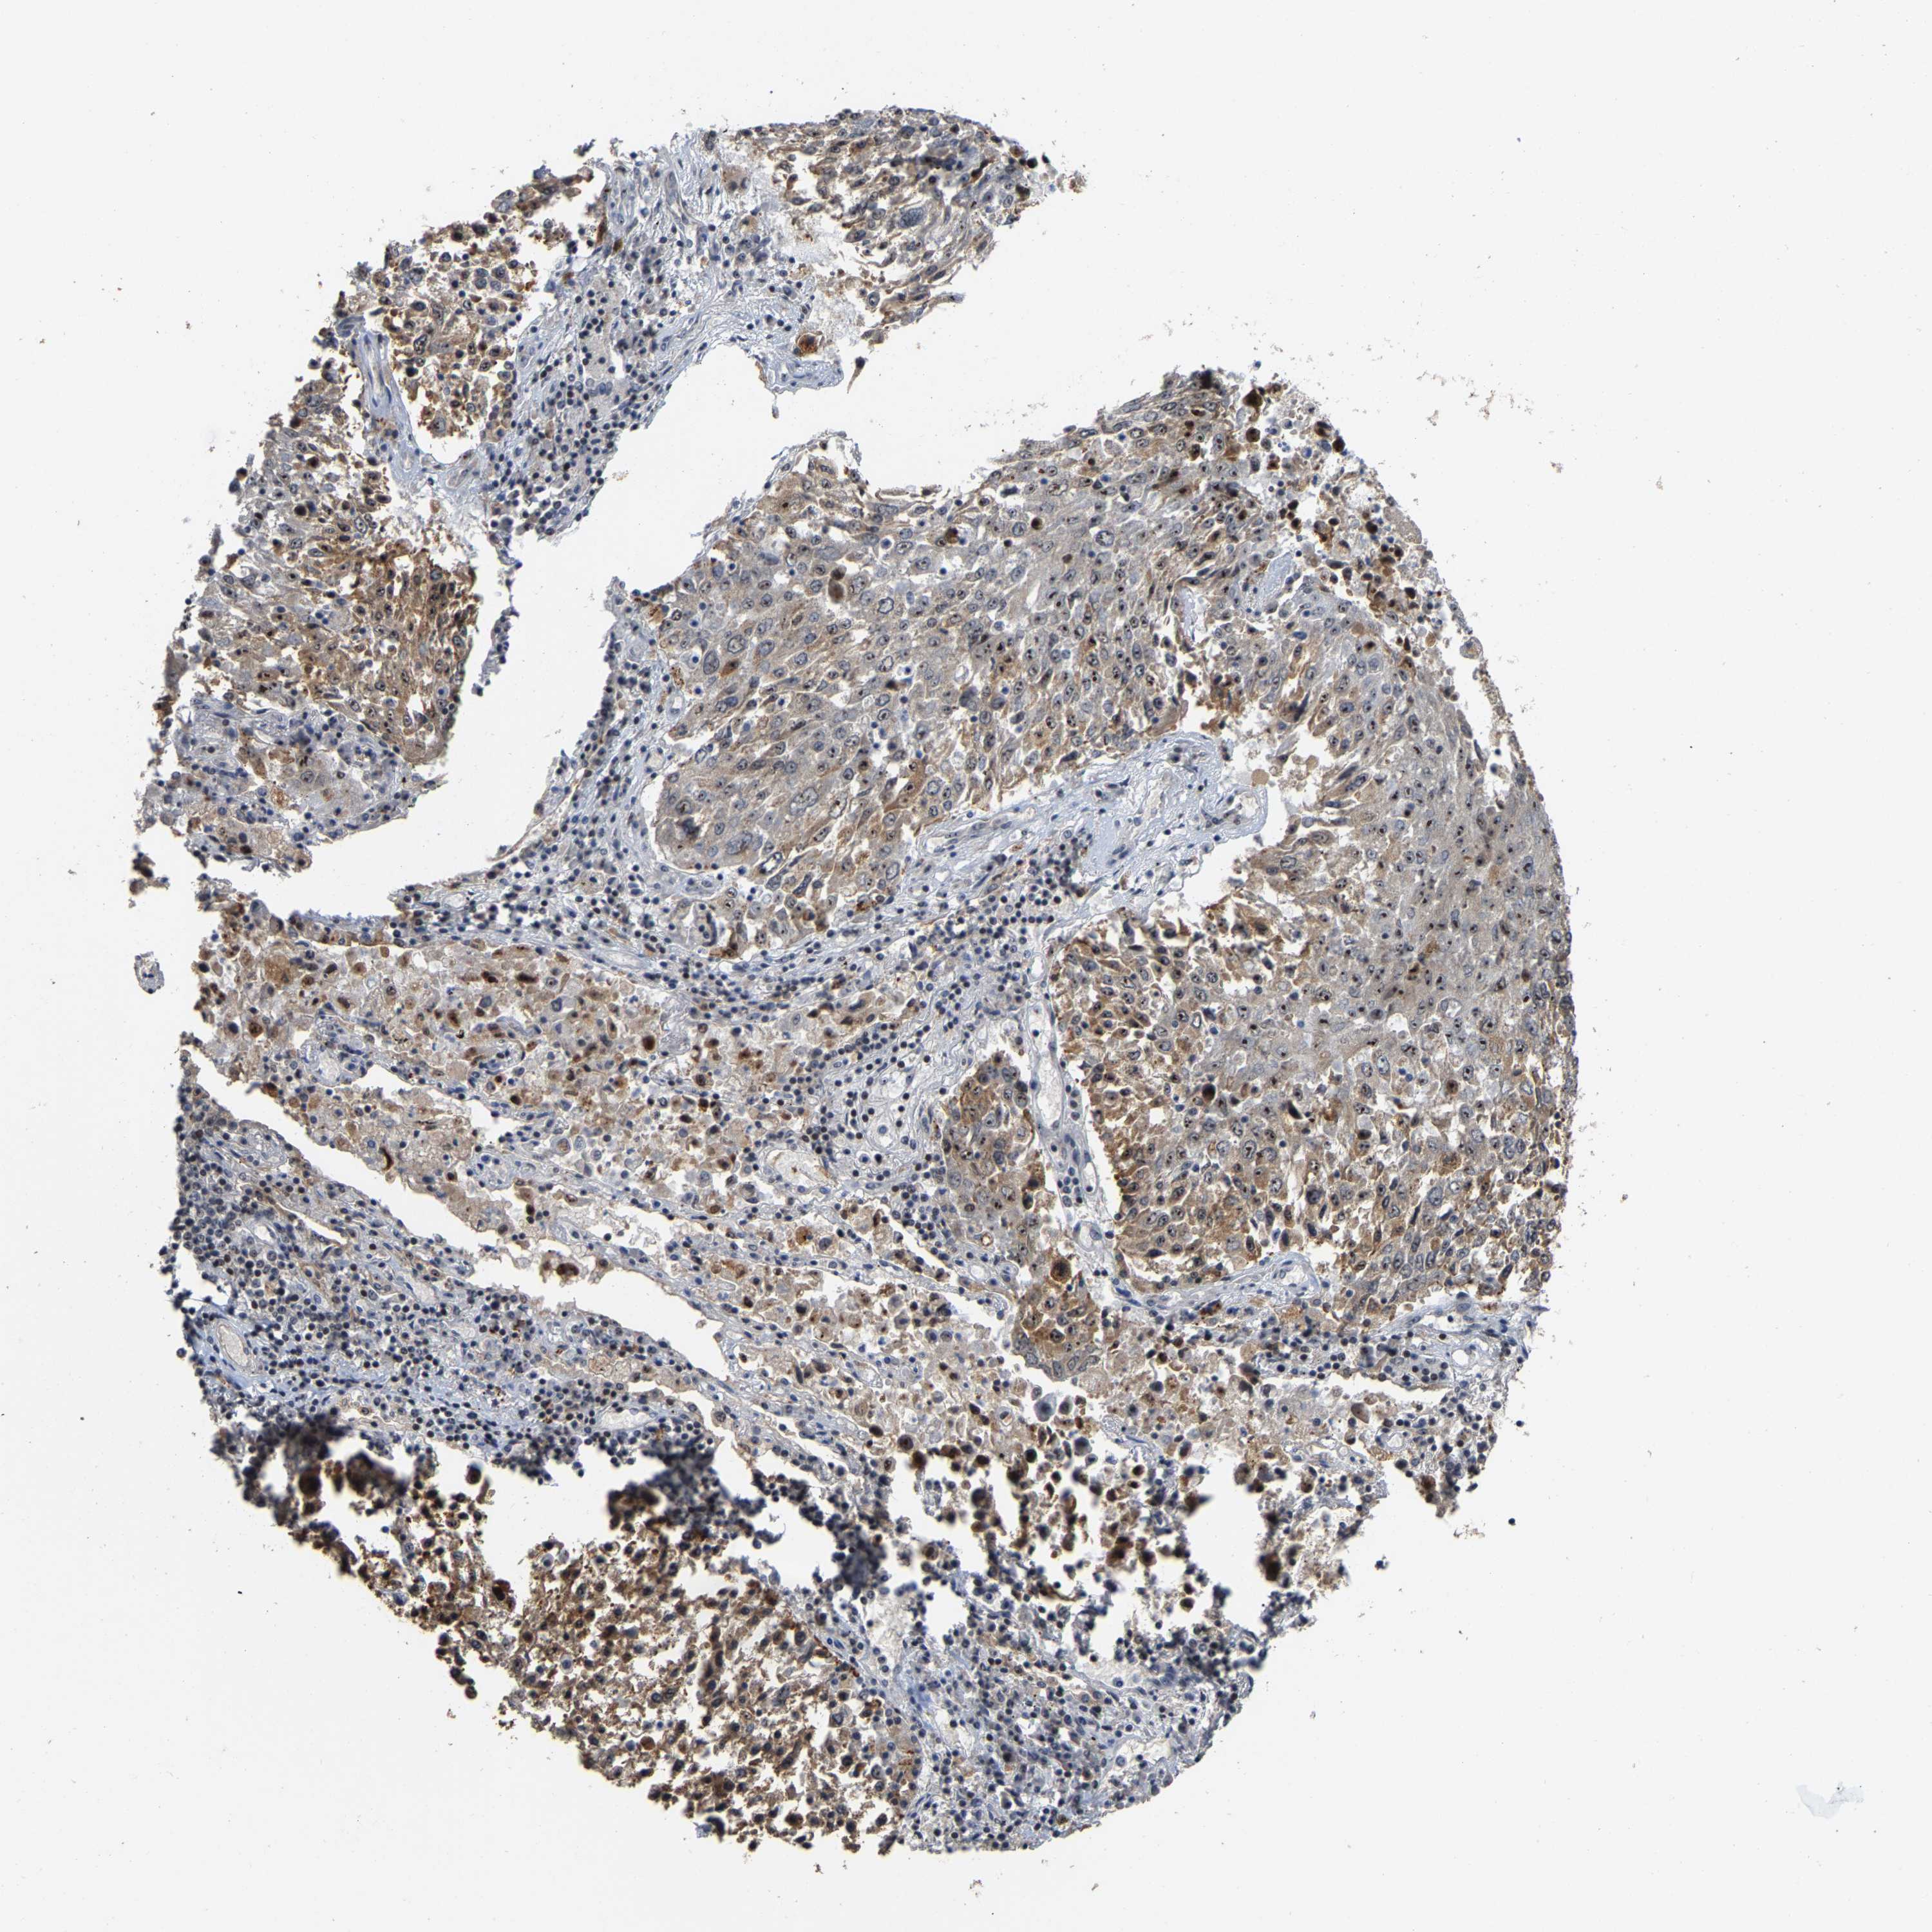

LUNG SQUAMOUS CELL CARCINOMA (TCGA) - Interactive survival scatter ploti

The Survival Scatter plot shows the clinical status (i.e. dead or alive) for all individuals in the patient cohort, based on the same data that underlies the corresponding Kaplan-Meier plots. Patients that are alive at last time for follow-up are shown in blue and patients who have died during the study are shown in red.

The x-axis shows the expression levels (FPKM) of the investigated gene in the tumor tissue at the time of diagnosis. The y-axis shows the follow-up time after diagnosis (years). Both axes are complimented with kernel density curves demonstrating the data density over the axes. The top density plot shows the expression levels (FPKM) distribution among dead (red) and alive patients (blue). The right density plot shows the data density of the survived years of dead patients with high and low expression levels respectively, stratified using the cutoff indicated by the vertical dashed line through the Survival Scatter plot. This cutoff is automatically defined based on the FPKM cutoff that minimizes the p-score. The cutoff can be changed by dragging the vertical line or by entering a cutoff value in the square labeled "Current cut-off".

Under the Survival Scatter plot the p-score landscape (black curve; left axis) is shown together with dead median separation (red curve; right axis). Dead median separation is the difference in median mRNA expression between patients who have died with high and low expression, respectively. It is calculated as follows: median FPKM expression of dead patients with high expression - median FPKM expression of dead patients with low expression. This is intended to aid the user in visually exploring custom cutoffs and the associated p-scores and dead median separation.

Individual patient data is displayed and can be filtered by clicking on one or more of the category buttons on the top of the page. Categories describing expression level and patient information include: high, low, alive, dead, female, male and tumor stages. The scale of the x-axis can be toggled between linear and log-scale by clicking on the "x log" button. Mouse-over function shows TCGA ID, patient information and mRNA expression (FPKM) for each patient.

& Survival analysisi

Kaplan-Meier plots summarize results from analysis of correlation between mRNA expression level and patient survival. Patients were divided based on level of expression into one of the two groups "low" (under cut off) or "high" (over cut off). X-axis shows time for survival (years) and y-axis shows the probability of survival, where 1.0 corresponds to 100 percent.

NOP58 is not prognostic in Lung Squamous Cell Carcinoma (TCGA)

: 47.86